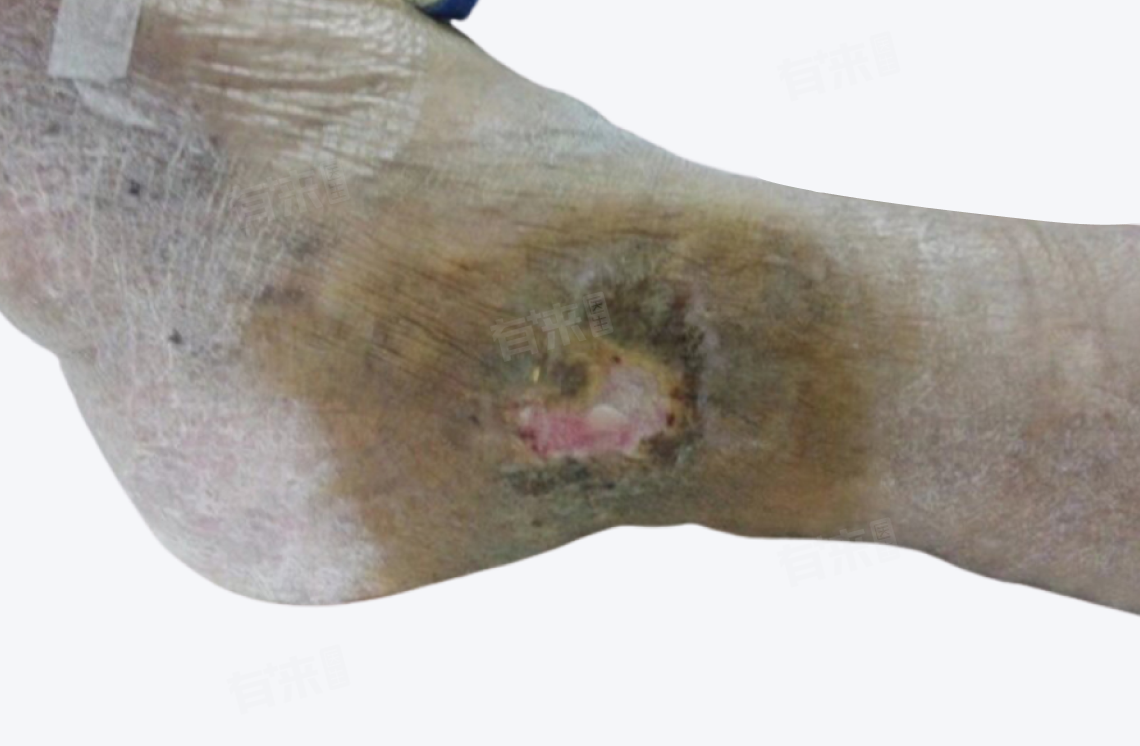

2、皮肤溃疡:当皮肤血管炎症较重时,可能会导致皮肤破溃形成溃疡。溃疡的大小、深度因病情而异,溃疡边缘通常不规则,底部可能有坏死组织,会有疼痛,并且愈合缓慢,容易反复。